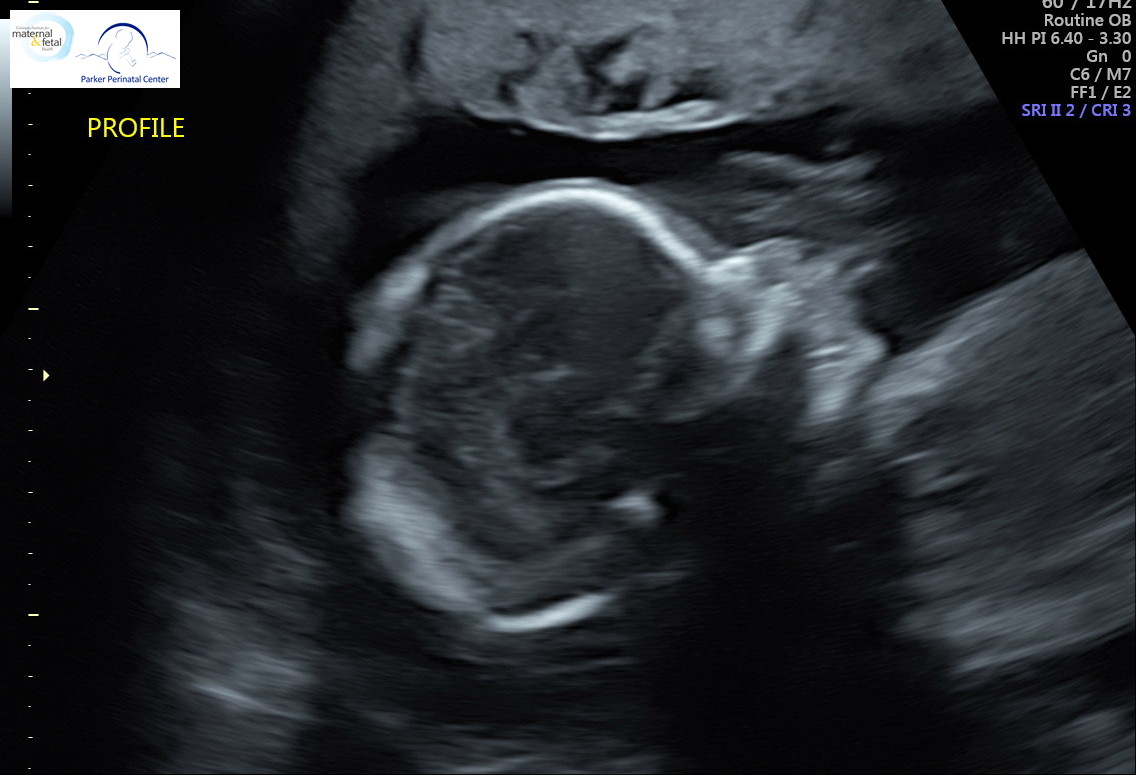

18 weeks after conception (20 weeks LMP), Baby Chris is about the size of a banana at 10 inches long from head to toe and 10 1/2 ounces. Circadian rhythm—the daily cycle of wakefulness and rest—shows up in Baby Chris’s movement and heart rate. You can also spot movement in Baby Chris’s vocal chords as he or she practices the muscle movements that will be necessary to make noise in the outside world.

It’s common for prenatal care providers to offer ultrasounds at this point in pregnancy, so we have an abundance of images this week. Here are just a few. Thank you to everyone who donated!